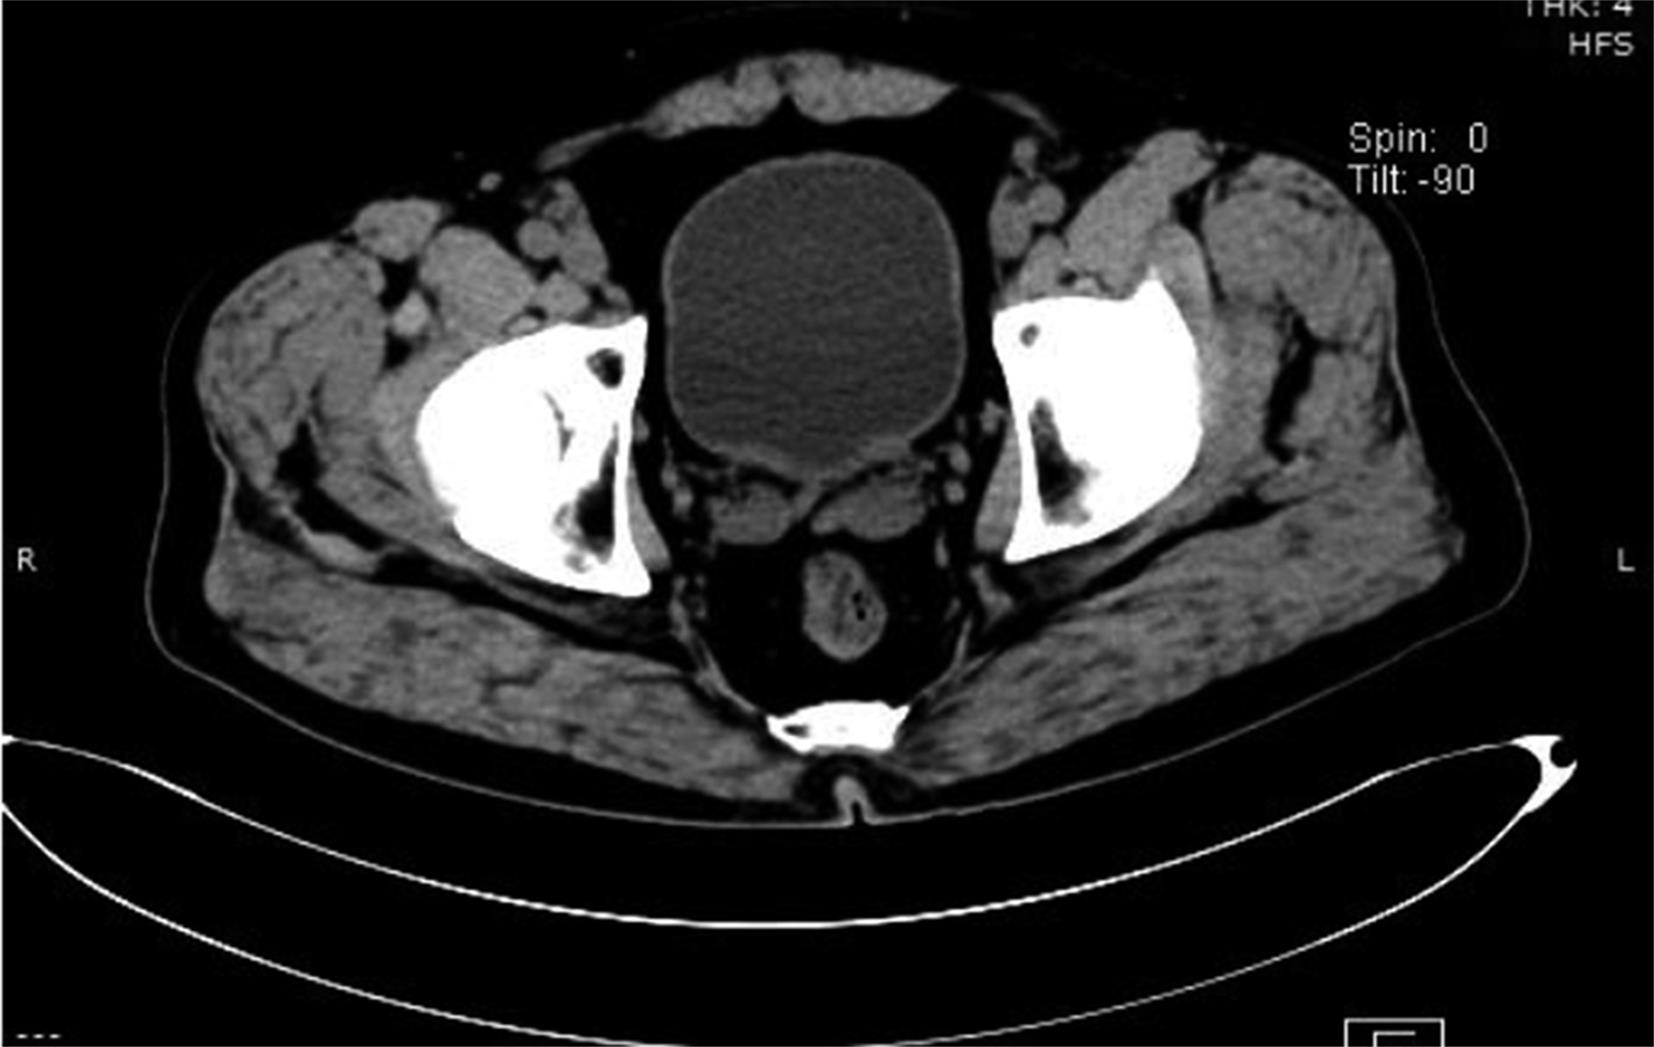

摘要:目的 探寻无法接受根治性手术治疗及放化疗的肌层浸润性膀胱癌病例的有效辅助治疗方式。方法 回顾性分析近10年广安门医院泌尿科肌层浸润性膀胱癌出院病例,统计患者治疗方式及保留膀胱时间。结果 61.90%应用膀胱肿瘤介入栓塞联合经尿道膀胱肿瘤切除术及中药治疗的患者达到了保留膀胱时间大于3年的治疗效果。结论 应用中西医结合治疗方式可能辅助延长肌层浸润性膀胱癌患者保留膀胱时间,改善患者预后及生存质量。